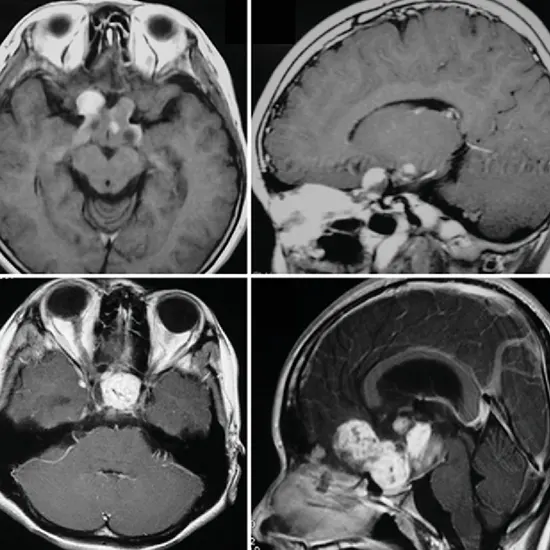

- Magnetic resonance imaging (MRI): This test produces specific photographs of the brain and visible pathway to observe any abnormalities.

- Magnetic resonance imaging (MRI): This produces unique pictures of the intelligence and hypothalamus to become aware of the presence of a tumor.